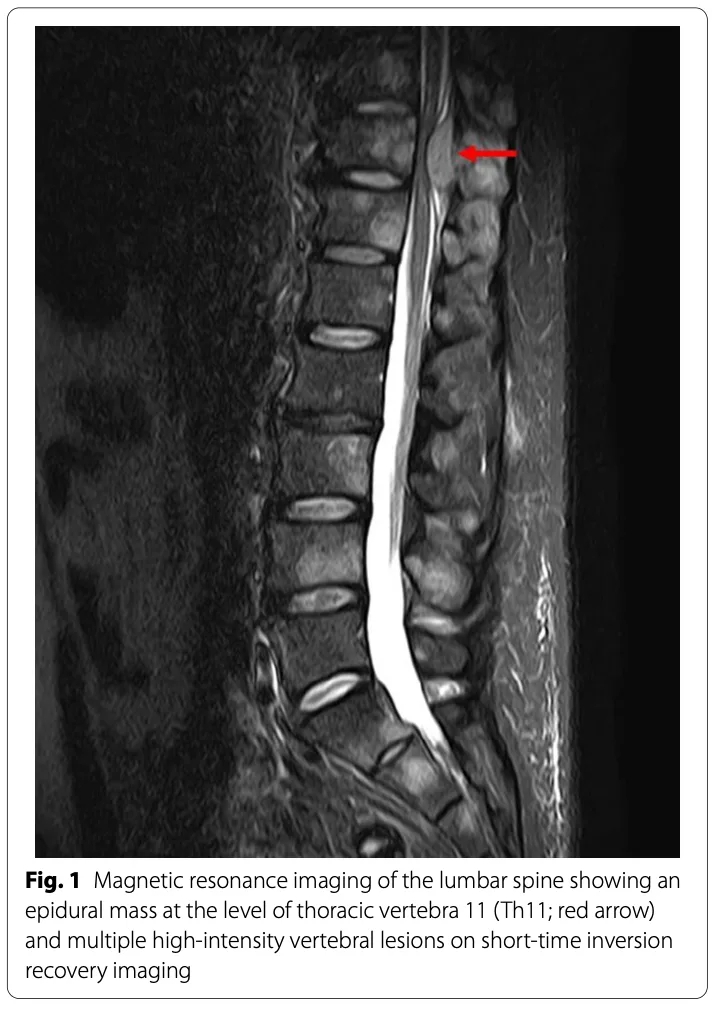

午前に搬送された腰痛患者のMRI結果を確認.

骨折はなく, 脊椎内に多数の円形陰影を認め, 大腸癌の既往から多発骨転移と診断.

後輩医師がオピオイド(麻薬様鎮痛薬)を処方し, 疼痛管理を開始しました.

骨の中の白く丸く写っている部分が癌の骨転移病巣です.